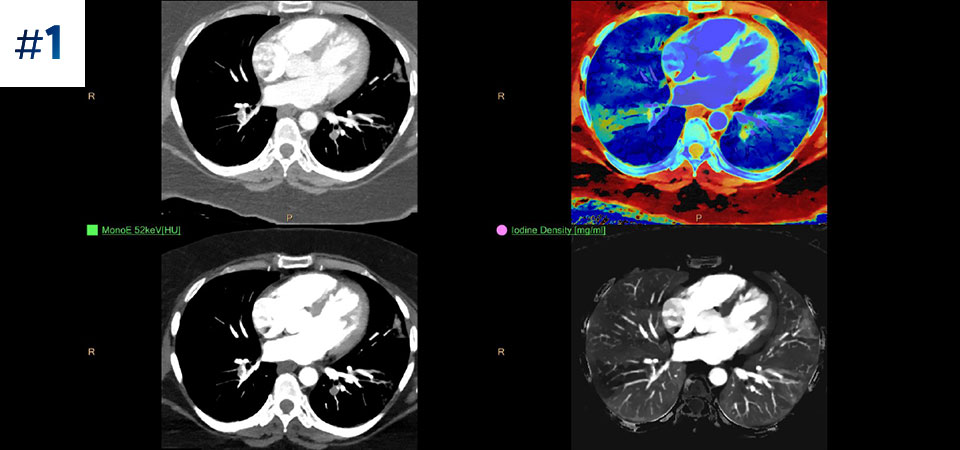

Observez la différence entre le scanner à détection spectrale et le scanner classique

Découvrez les avantages du scanner à détection spectrale